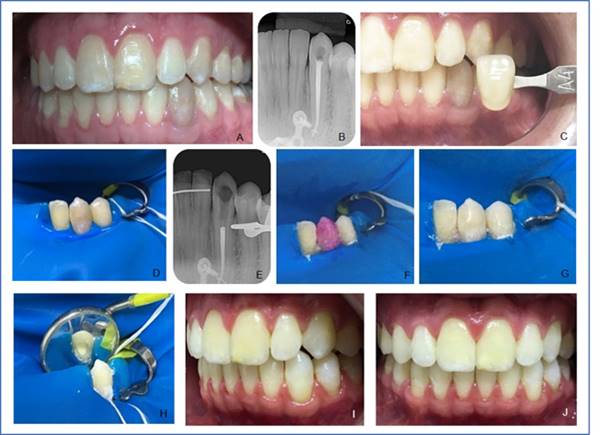

Clinical case 1 report: 23-year-old male with Treacher Collins Syndrome attending Hospital de Reabilitação de Anomalias Craniofaciais, University of São Paulo (HRAC/USP). He reports a chromatic change in the lower left canine (33) (Fig. 1, A). This was verified on clinical examination, as well as absence of painful symptoms. Satisfactory endodontic treatment was observed on radiographic examination (Fig. 1, B). Internal bleaching was performed with the mixed technique. The color (A4) was selected using the VITA scale (Wilcos do Brasil, Petrópolis RJ, Brazil). There followed an intraoral photo (Fig. 1, C), absolute isolation (Fig. 1, D), followed by access to the pulp chamber using diamond bur No. 1012 (KG Sorensen Ind. Com. Ltda, Barueri, Brazil). Endodontic obturation was removed at approximately 3 mm deep with No. 2 condensers heated at the root canal entry, the cavity was cleaned, and the cervical barrier was prepared (Figure, E) with glass ionomer cement (FGM, Joinville, SC, Brazil). Acid etching of the pulp chamber was then performed with 37% phosphoric acid (Biodynamics, Ibiporã, PR, Brazil) for 30 seconds, then washed with plenty of water for 60 seconds and dried with an air jet. This is done to remove the smear layer, open the dentinal tubules and therefore increase the dentin's permeability to the bleaching agent. We handled 35% hydrogen peroxide gel (Whiteness HP, FGM, Joinville, SC, Brazil) following the manufacturer’s guidelines and placed it inside the pulp chamber and on the buccal face with a medium-sized microbrush (KG Sorensen Ind. Com. Ltda, Barueri, Brazil) for 45 minutes (Fig. 1, F and G). The gel was removed by washing with water for 1 minute, and then a granular sodium perborate paste (Pharmacy Specific, Bauru, SP, Brazil) was handled with sterile saline solution in a sterile Dappen glass. The paste was placed inside the pulp chamber with an insertion spatula and evenly spread (Fig. 1, H). The tooth was sealed with glass ionomer cement (FGM, Joinville, SC, Brazil). A satisfactory result was observed after seven days (Figs. 1, I and J) when comparing the tooth to its past appearance. Calcium hydroxide paste (Calen) (SSWhite Duflex, São Cristovão, RJ, Brazil) was applied. The temporary restoration with glass ionomer cement (FGM, Joinville, SC, Brazil) was placed. The patient reported the yellowing of the other teeth and was then referred to the Aesthetic Dentistry sector of HRAC/USP for external whitening and for the final restoration.